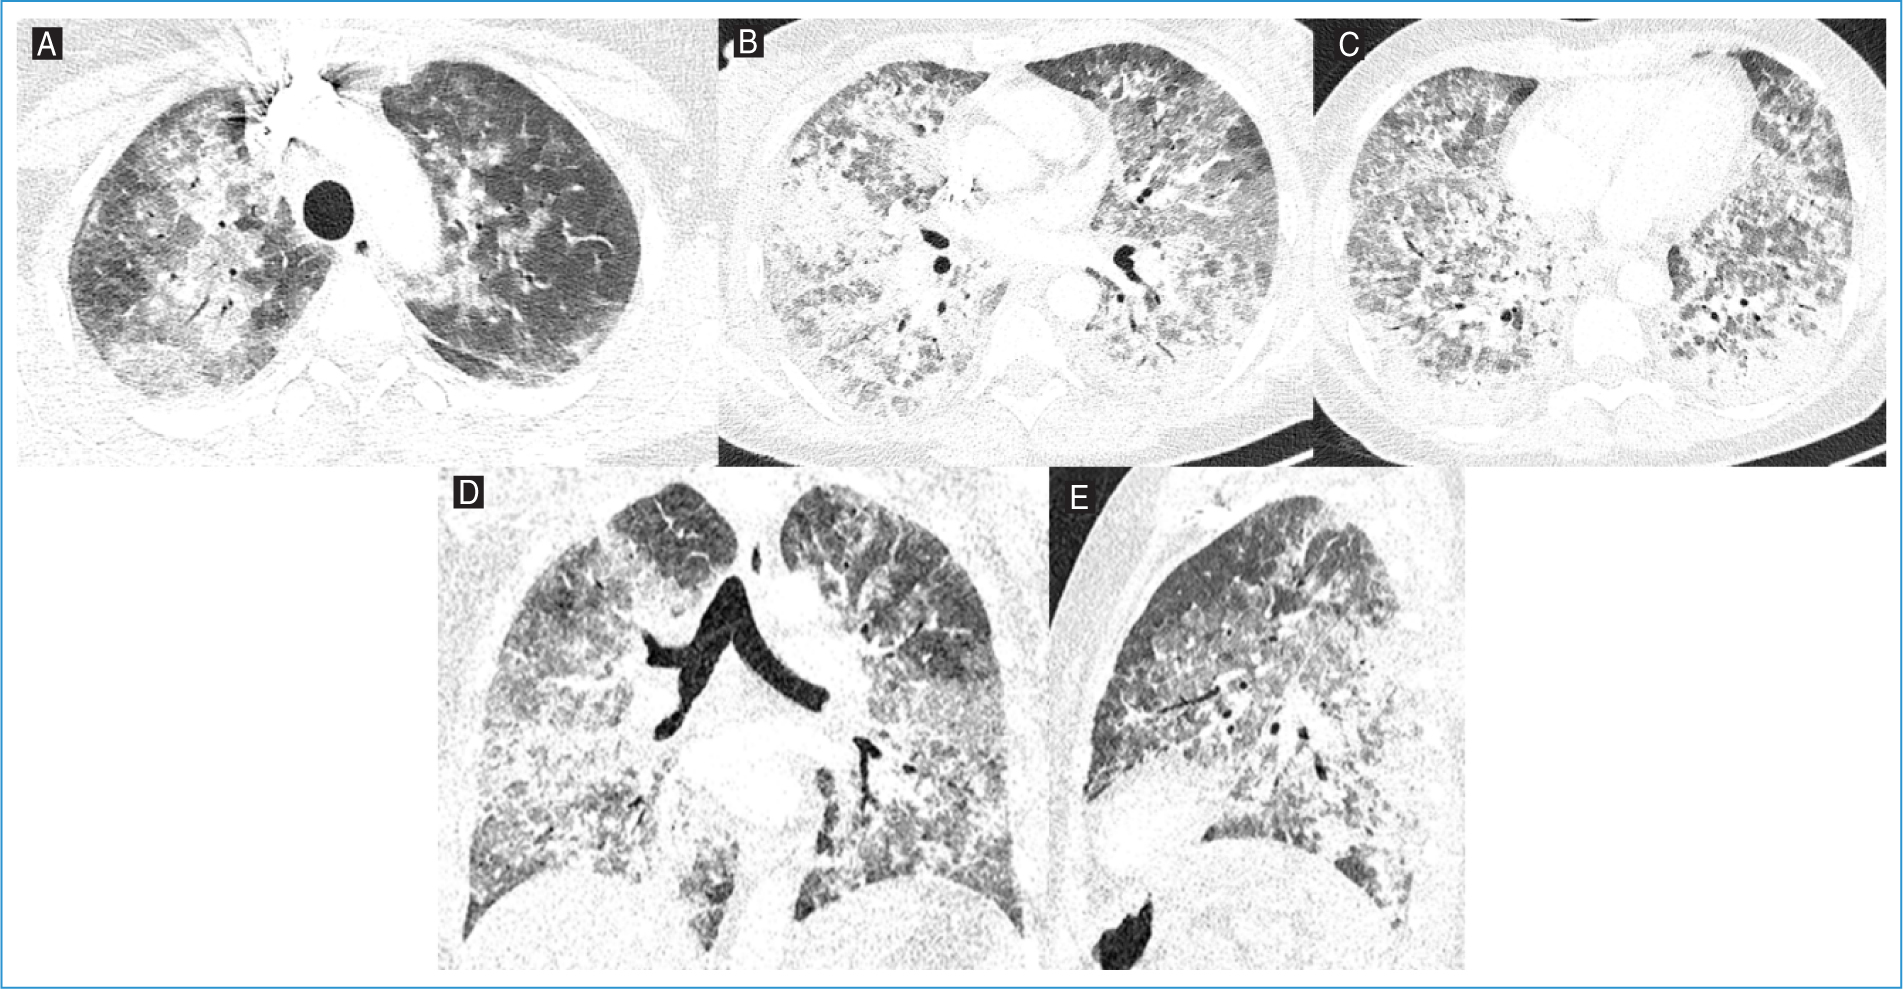

A contrast-enhanced thoracic computed tomography (CT) scan revealed diffuse ground-glass opacities, predominantly in the middle and lower lung lobes and, in a perihilar distribution, multiple areas of established consolidation (Fig. 1). Testing for respiratory viruses such as SARS-CoV-2, Influenza A/B, and respiratory syncytial virus was negative. A flexible bronchoscopy was performed, and P. jirovecii was isolated in the bronchoalveolar lavage fluid (BAL). She was started on trimethoprim-sulfamethoxazole (TMP-SMZ) and methylprednisolone, with progressive clinical, laboratory, and radiological improvement.

Figure 1. Axial lung window images of the A: upper, B: middle, and C: lower levels, along with D: coronal and E: sagittal reconstructions from thoracic computed tomography angiography of Patient #1. Diffuse ground-glass opacities are observed, predominantly in the middle and lower lung zones and in a perihilar distribution, with multiple areas of consolidation.